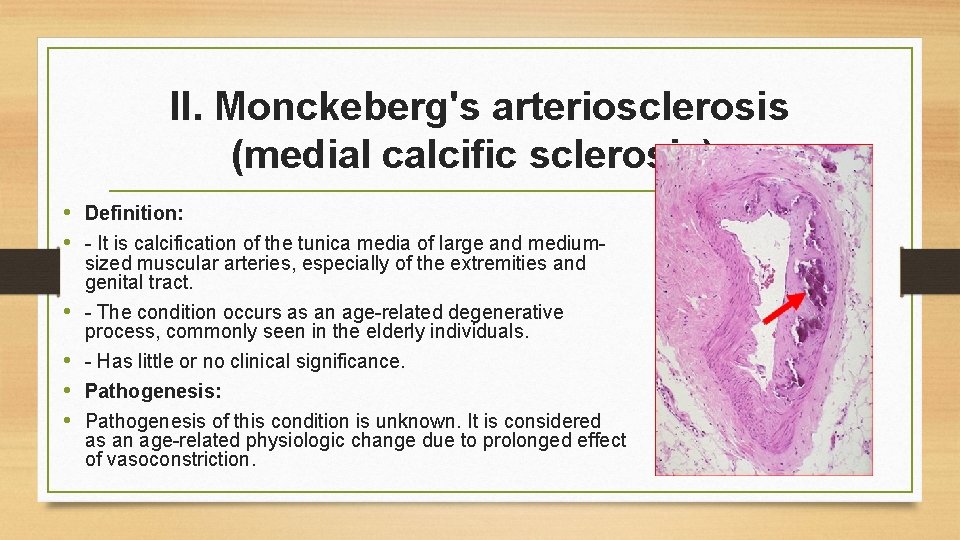

II. Monckeberg's arteriosclerosis (medial calcific sclerosis): • Definition: • - It is calcification of the tunica media of large and mediumsized muscular arteries, especially of the extremities and genital tract. • - The condition occurs as an age-related degenerative process, commonly seen in the elderly individuals. • - Has little or no clinical significance. • Pathogenesis: • Pathogenesis of this condition is unknown. It is considered as an age-related physiologic change due to prolonged effect of vasoconstriction.